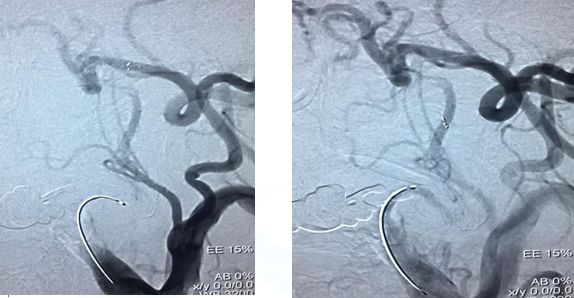

造影示:颈内动脉闭塞,眼动脉有代偿,血管闭塞原因决定血管再通方式!

找到闭塞血管部位,狭窄?夹层?

在颈内远端用6*30Solitaire逐次向近端释放支架(夹层可能性大)

支架释放状态血管通畅,逐渐找到血管闭塞部位

支架在病变最近端释放

11-3,21:40:血管再通,支架释放解脱